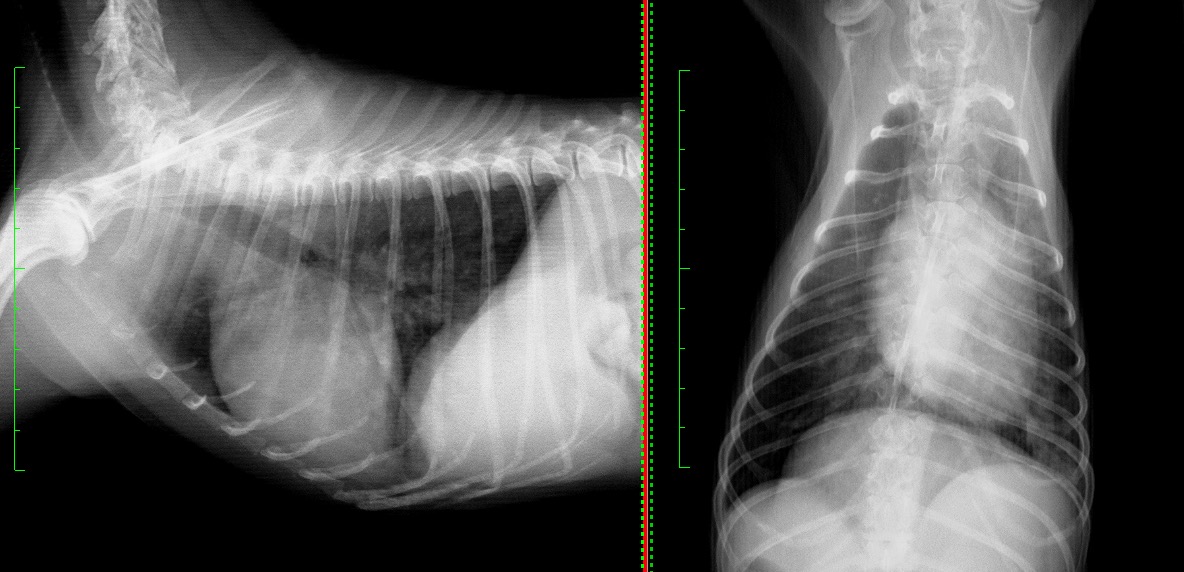

退院時の胸部X線検査では、肺野の不透過性が大きく改善しているのが見て取れます。